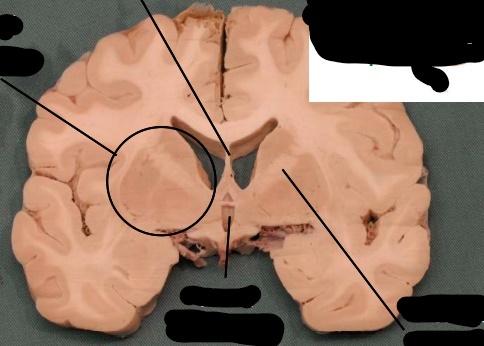

label, note important features

uncus is seen on the ventral (inferior) surface of cerebram, pointing towards the mamillary bodies or optic chiasm. following the uncus, the change in the basic organization of cortex indicates the hippocampus